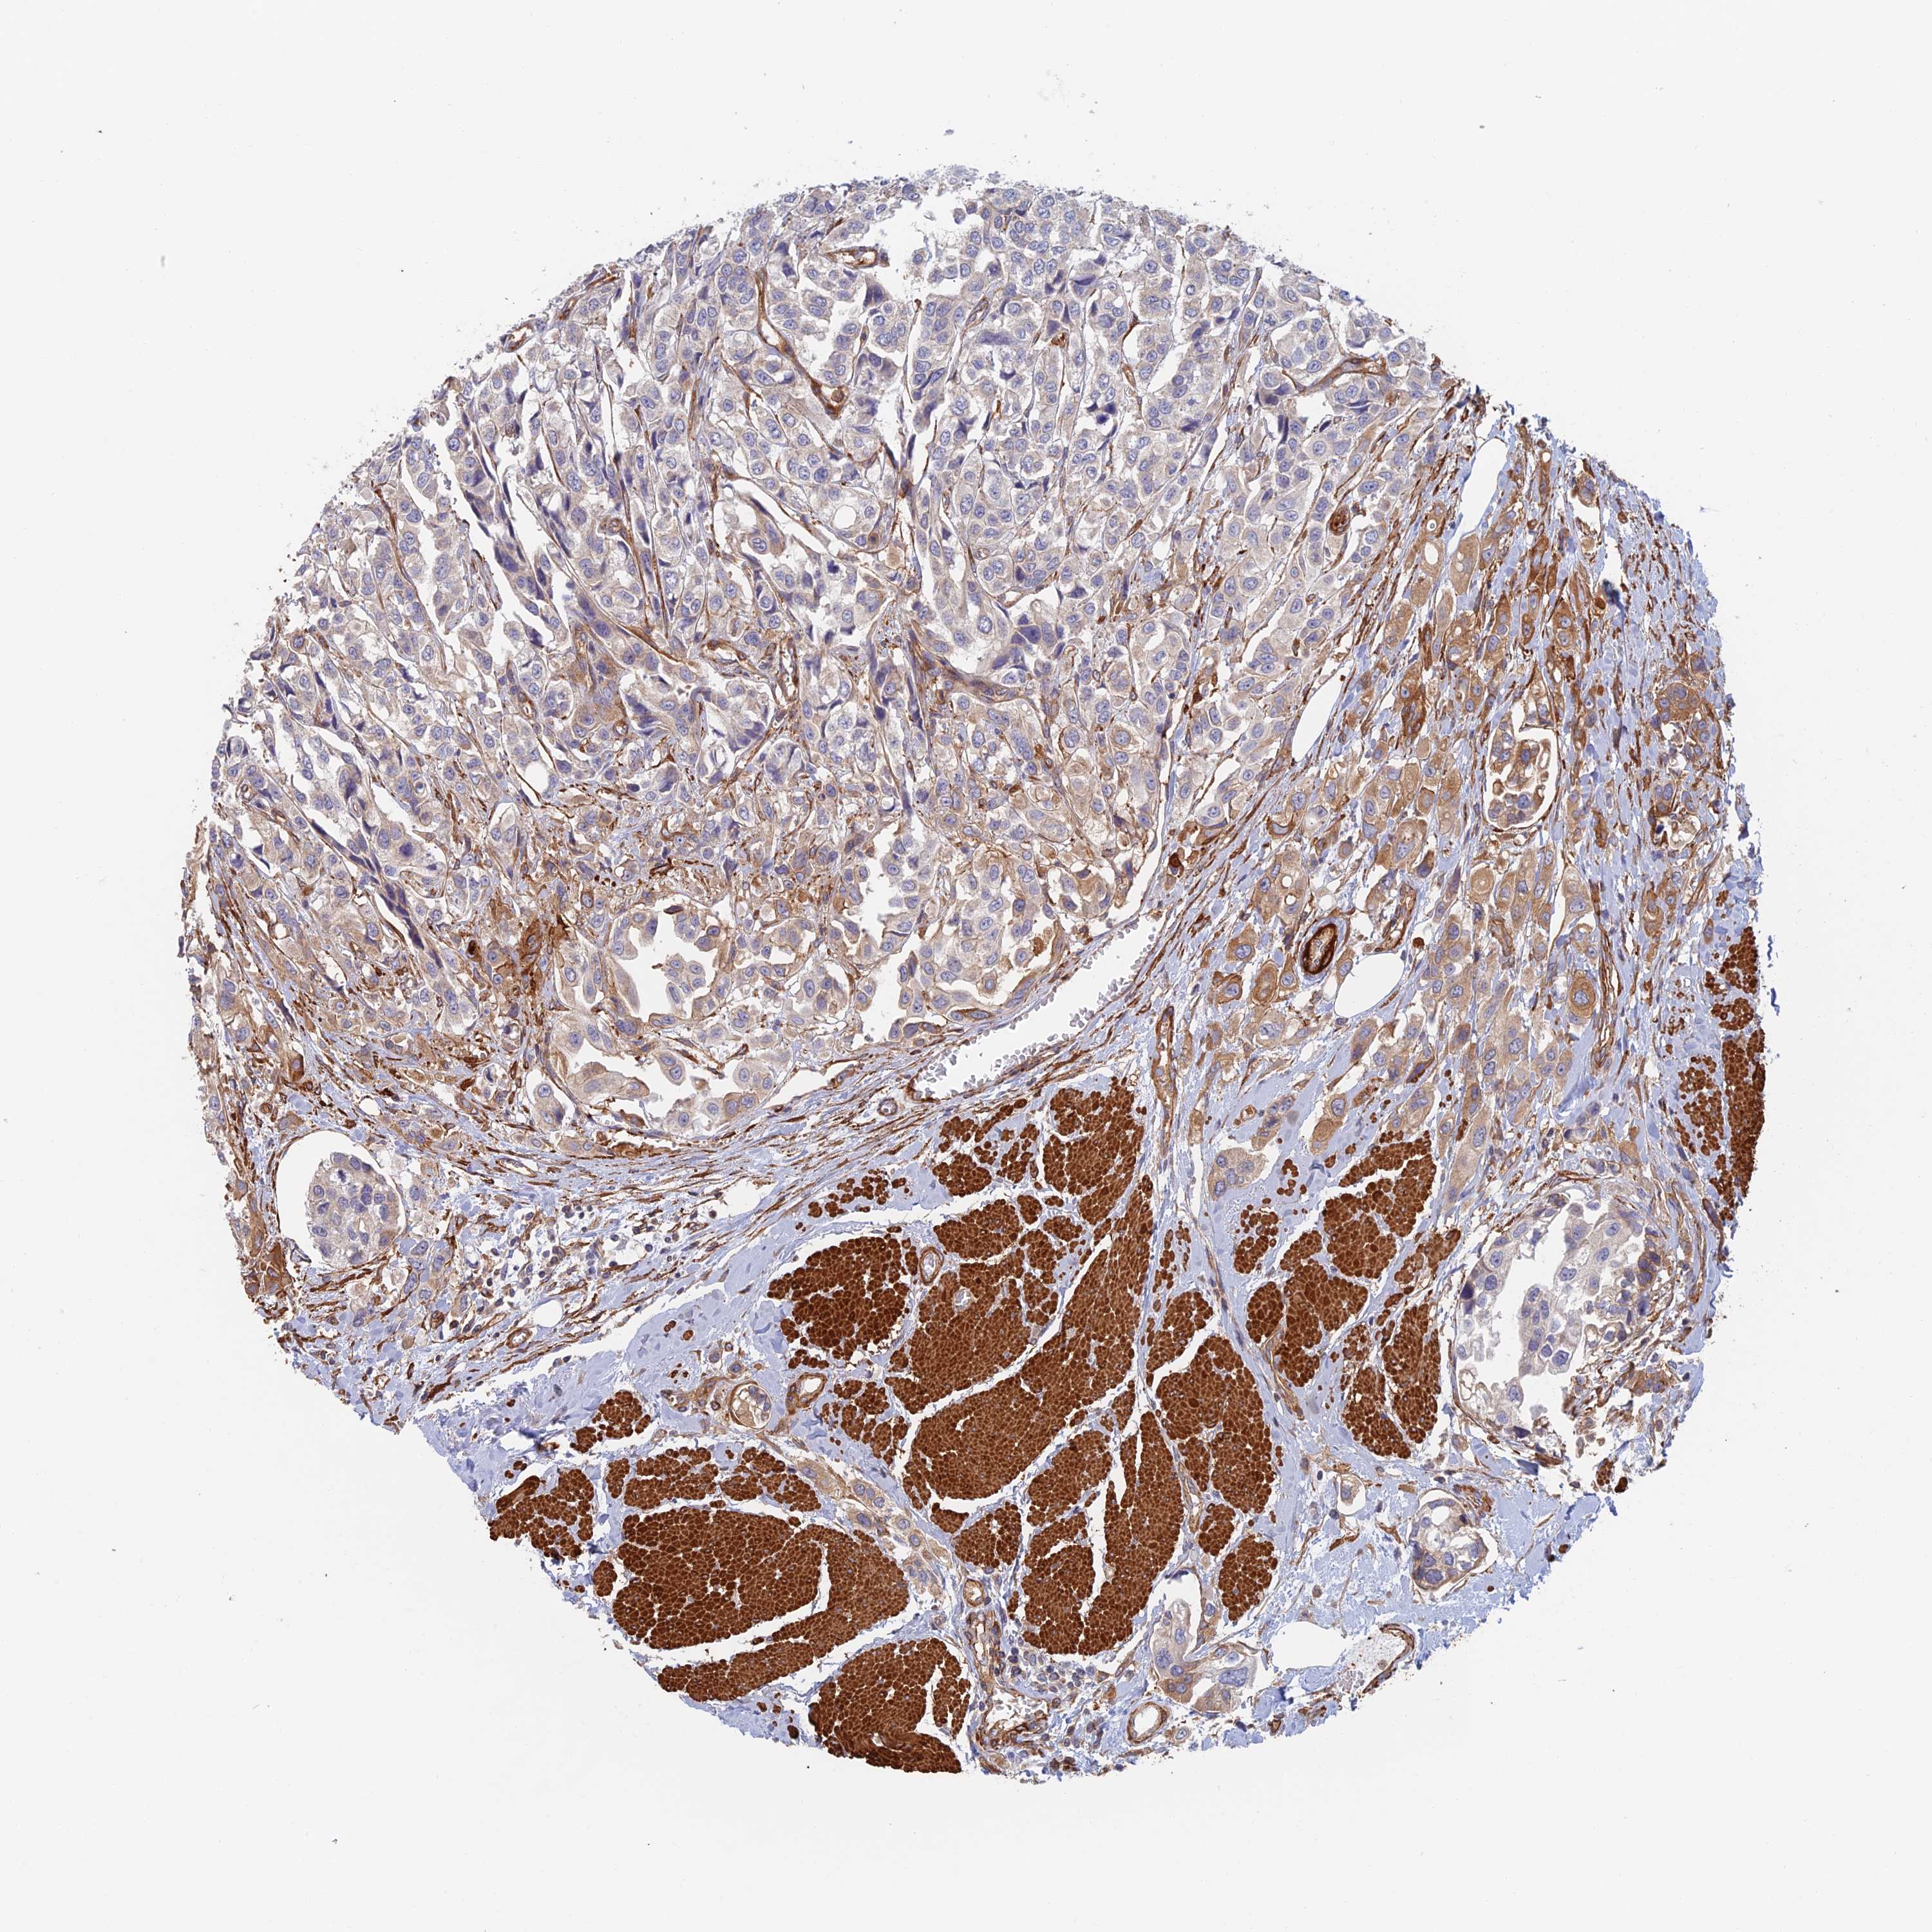

UROTHELIAL CANCER - Protein expressioni

A mouse-over function shows sample information and annotation data. Click on an image to view it in a full screen mode. Samples can be filtered based on level of antibody staining by selecting one or several of the following categories: high, medium, low and not detected. The assay and annotation is described here.

Note that samples used for immunohistochemistry by the Human Protein Atlas do not correspond to samples in the TCGA dataset.

Antibody stainingi

Antibody staining in the annotated cell types in the current human tissue is reported as not detected, low, medium, or high, based on conventional immunohistochemistry profiling in selected tissues. This score is based on the combination of the staining intensity and fraction of stained cells.

Each image is clickable and will lead to virtual microscopy that enables deeper exploration of all samples and also displays staining intensity scores, fraction scores and subcellular localization as well as patient and tissue information for each sample.

Antibody CAB025747

Antibody CAB044670

Staining

High

Medium

Low

Not detected

Intensity

Strong

Moderate

Weak

Negative

Quantity

>75%

75%-25%

<25%

None

Location

Nuclear

Cytoplasmic/membranous

Cytoplasmic/membranous,nuclear

Urothelial carcinoma, Low grade

Urothelial carcinoma, High grade